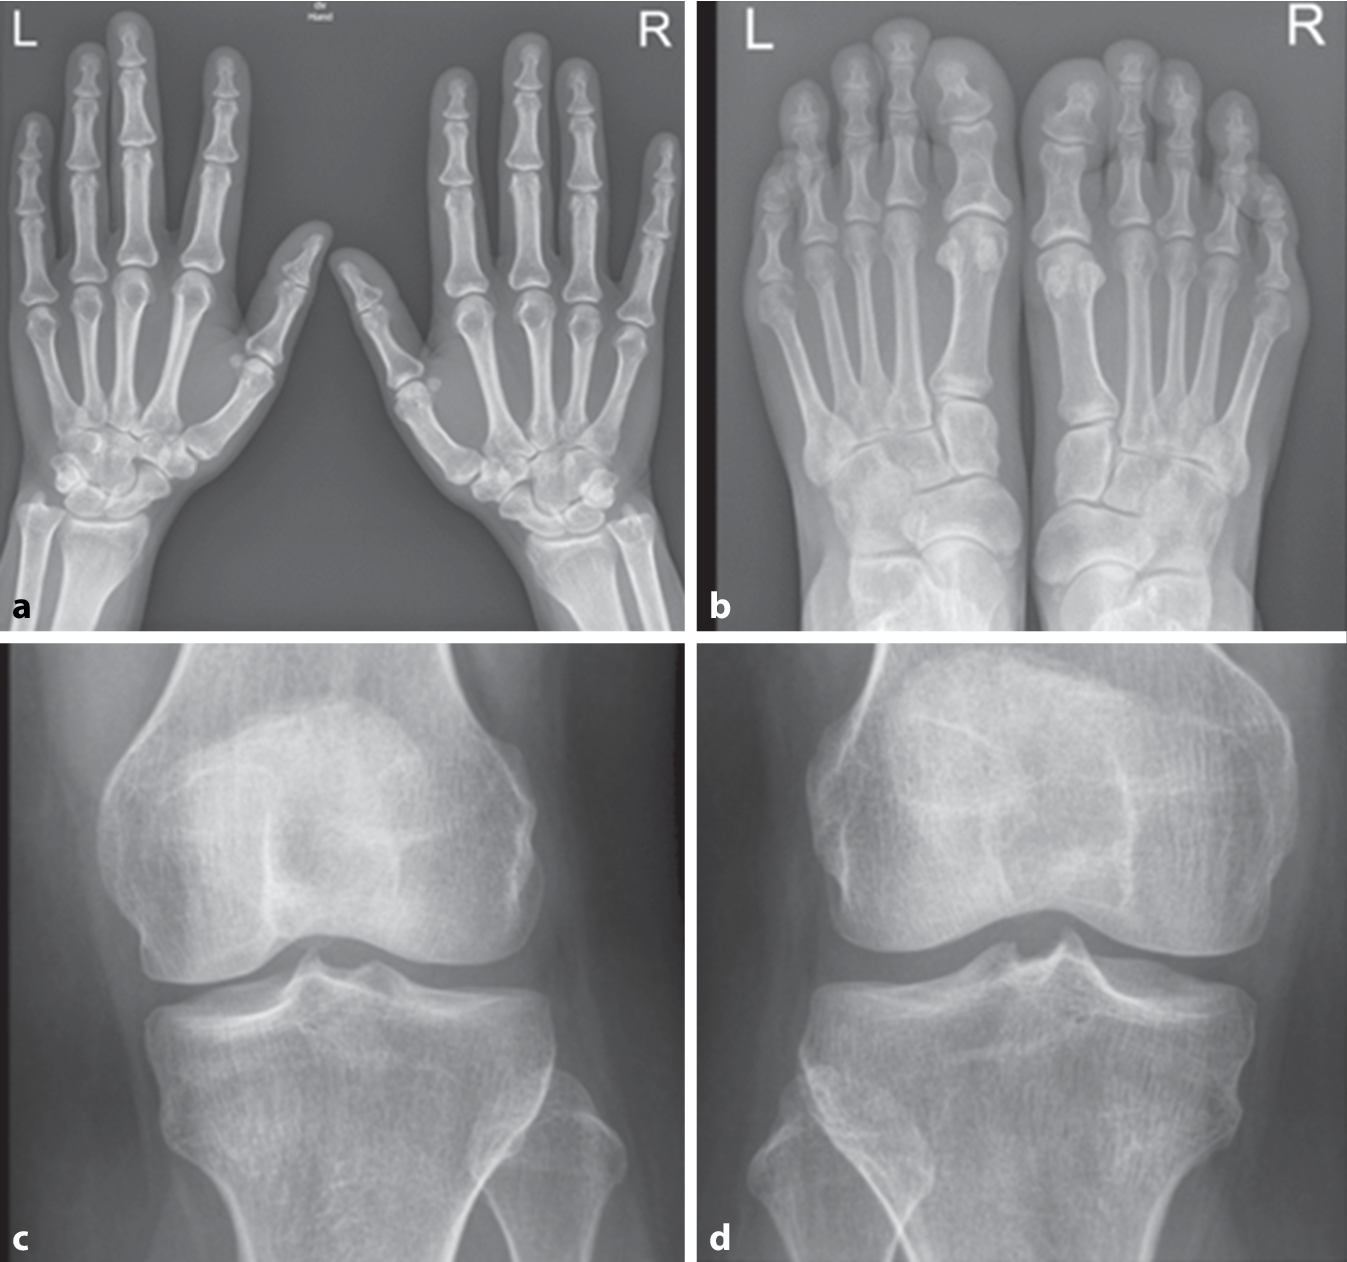

Nativradiologisch bestanden keine typischen arthritischen Veränderungen der Hände und Füße noch Zeichen einer Kristallarthropathie der Knie und Hände (Abb. 1). Bei normwertiger Nierenfunktion und unauffälligem Urinsediment konnten in der Abdomensonographie kleine Konkremente im Nierenbeckenkelchsystem (Nierengrieß) beidseits ohne Harnstauung dargestellt werden (Abb. 2). Zudem ergab sich elektroneurographisch kein Hinweis auf ein Karpaltunnelsyndrom bei ebenfalls unauffälligem Befund der Magnetresonanztomographie der Lendenwirbelsäule.

Abb. 1

Konventionelle Röntgenaufnahmen der a Hände und b Füße beidseits mit unspezifischen Veränderungen. An den Knien (c links und d rechts) beidseits keine Meniskusverkalkung als Hinweis auf eine Kalziumpyrophosphat-Dihydrat(CPPD)-Arthropathie